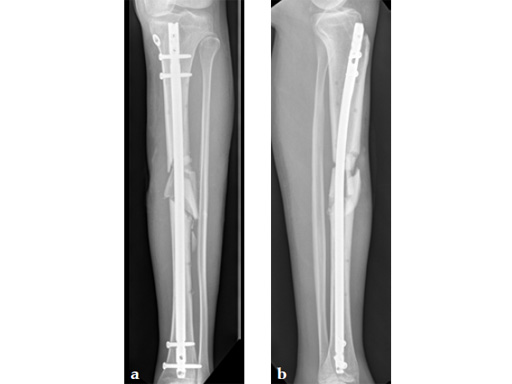

Case 1: A 33-year-old man with a third degree open fracture of his left tibia was initially treated with an external fixator and unilateral compartment release. He had undergone ACL reconstruction in the past.